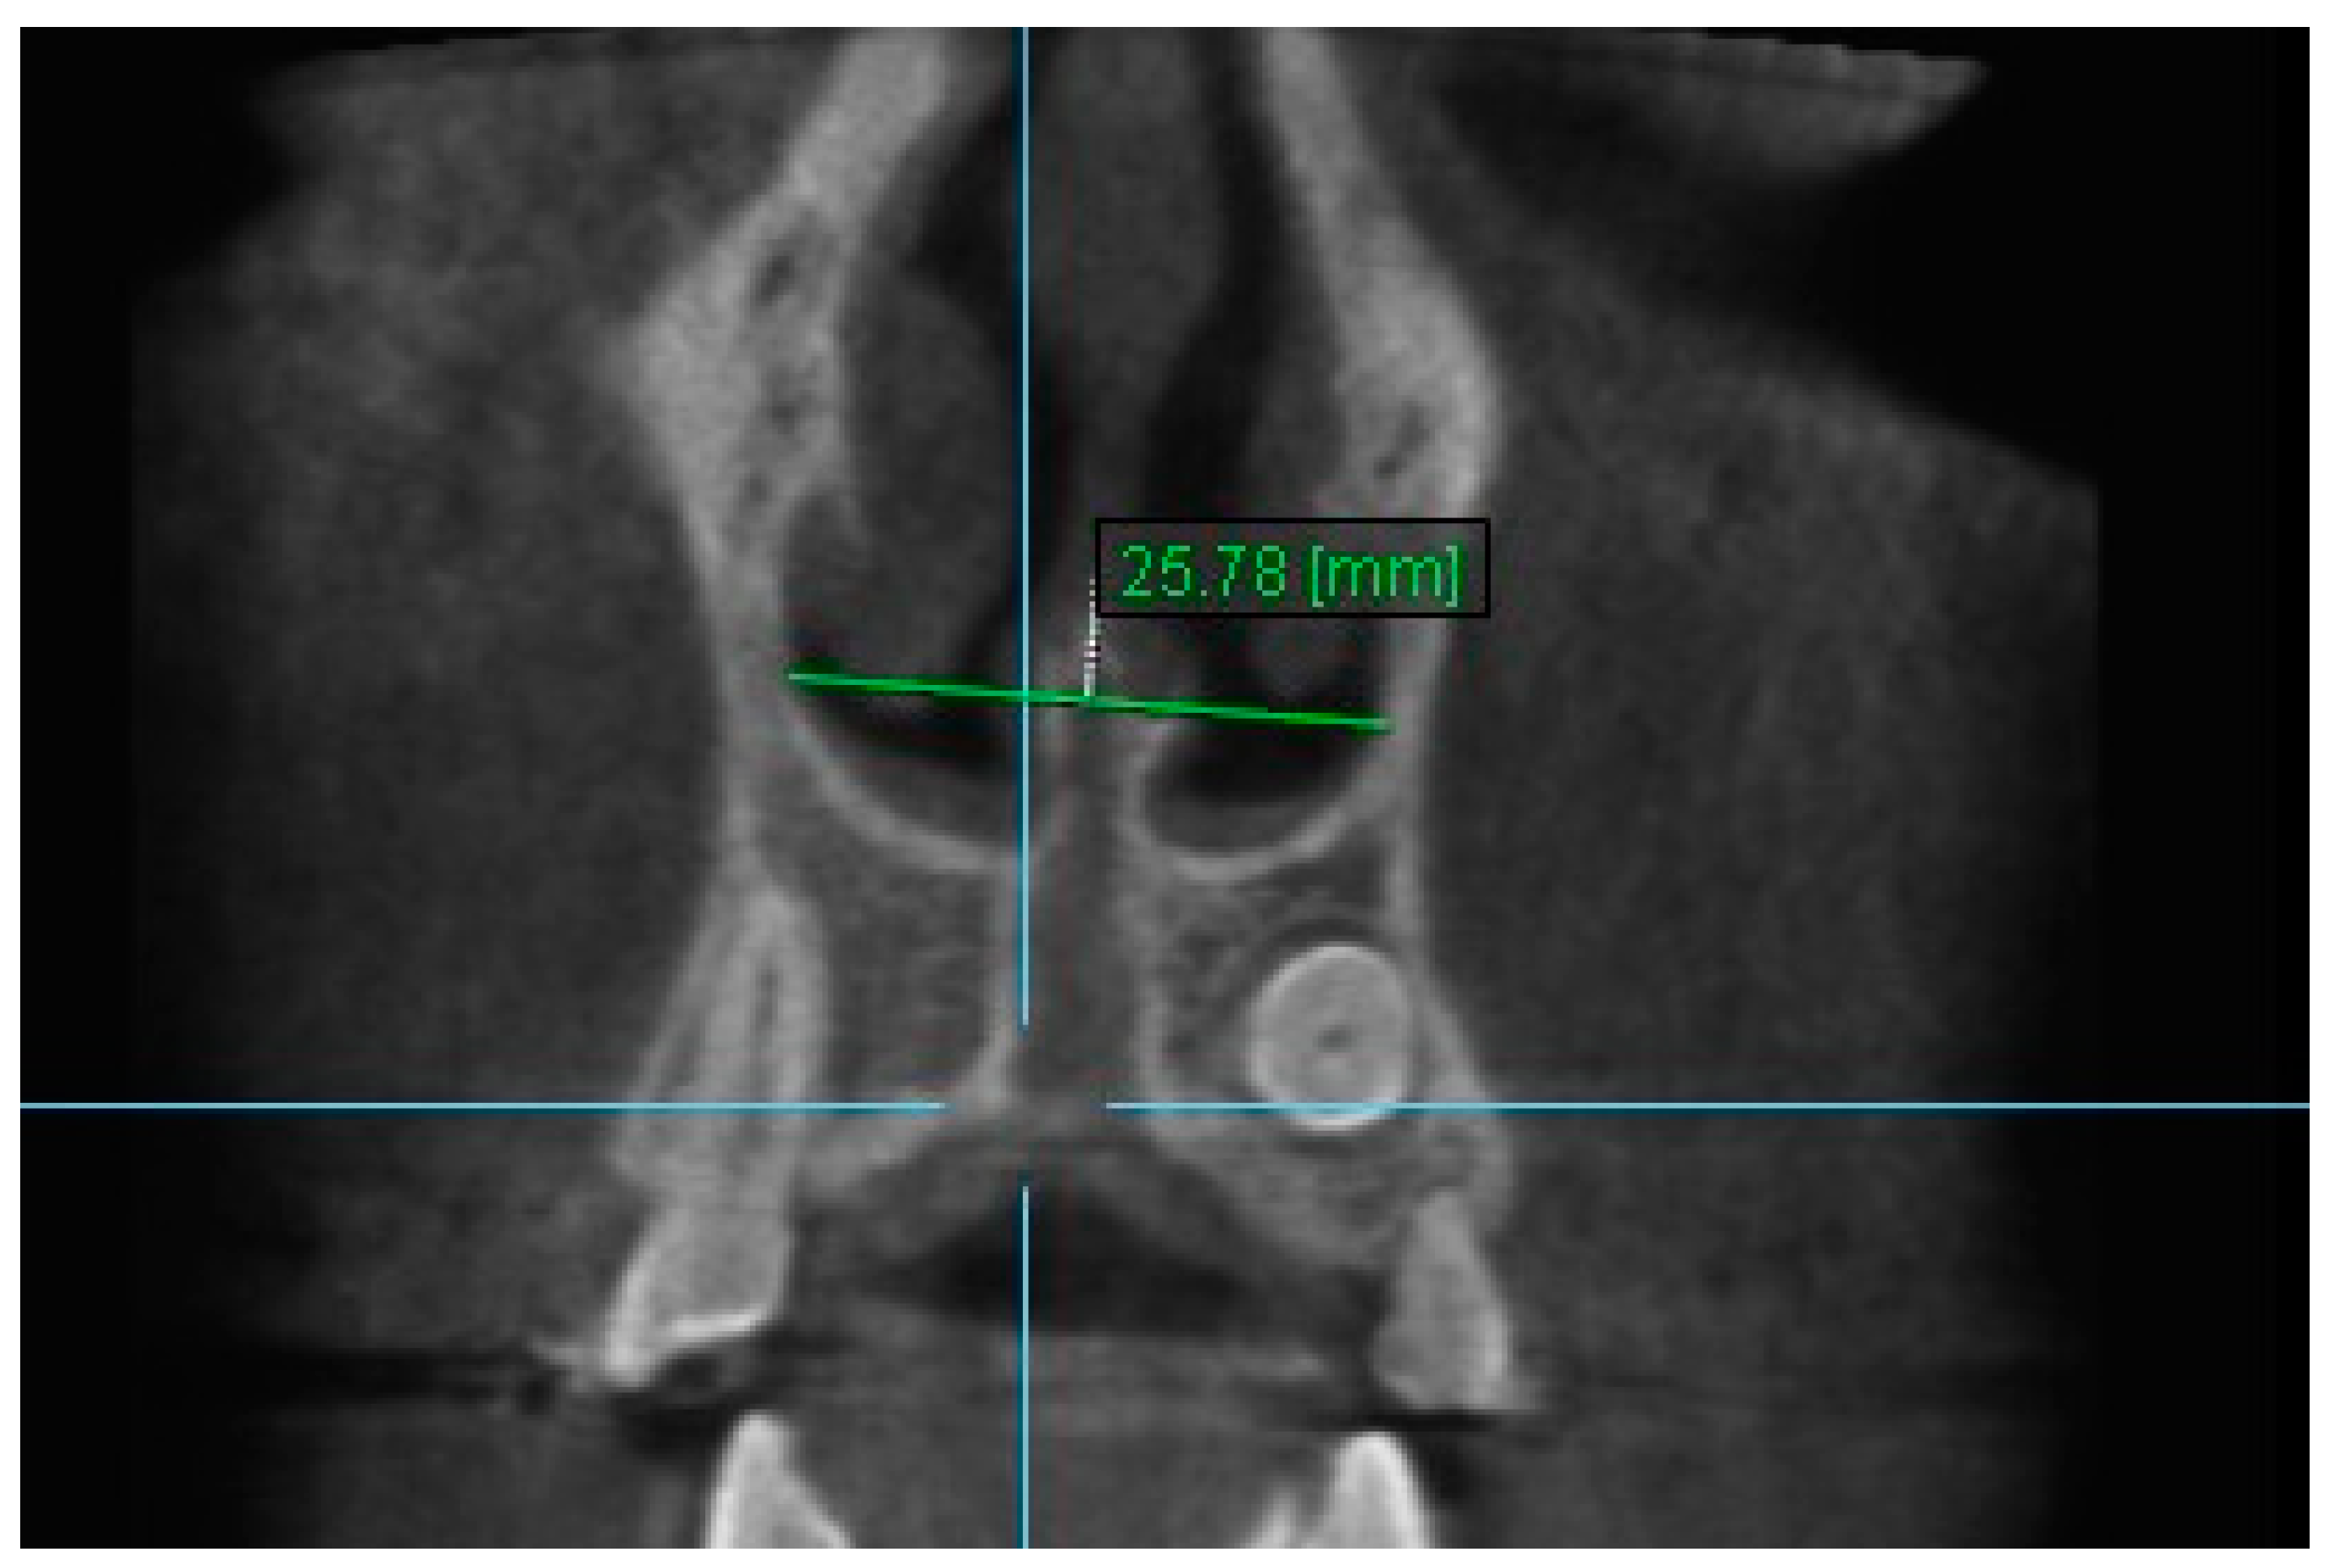

| Nasal Floor 9 | T1 | 15.75 ± 3.69 | 15.67 ± 3.51 | 0.995 (0.984–0.998) |

| T2 | 18.52 ± 3.21 | 18.42 ± 2.88 | 0.991 (0.974–0.997) | |

| T3 | 17.18 ± 3.51 | 17.37 ± 3.39 | 0.990 (0.958–0.997) | |

| Nasal Floor 9 | 13.61 | 16.60 | 15.11 | 2.99 | ** | 1.51 | *** | −1.49 | ** |